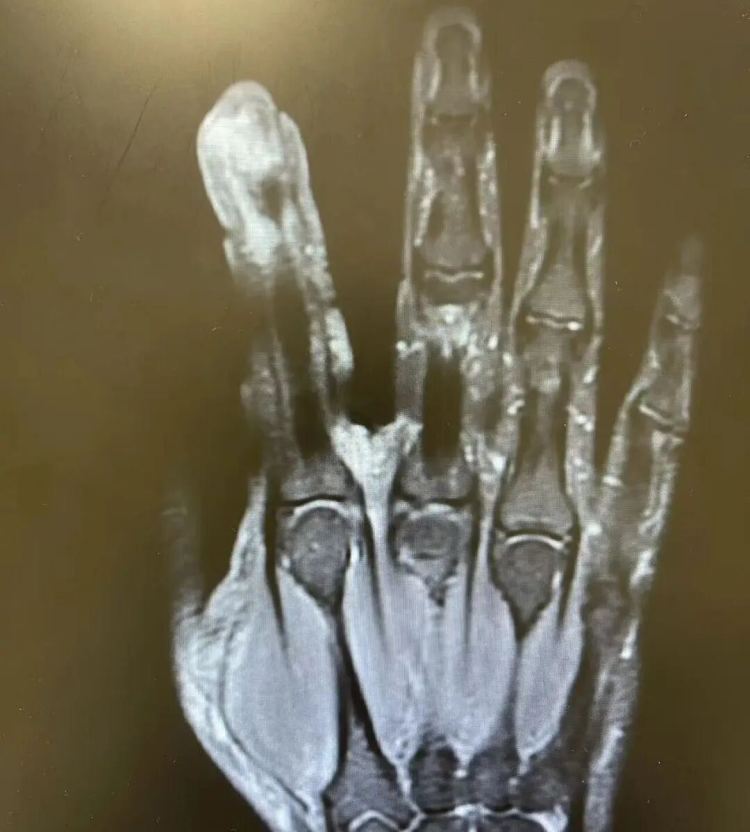

历程一系列搜检,李老迈破溃的左手指尖严重感染,厌氧消化链球菌顺着龙套处钻到骨头里,激励了严重骨髓炎,“再晚一步,就会有截肢风险!”卢荟淡薄李老迈必须先手术清创再逢迎抗感染调养才智出险。因为跟着骨髓炎细菌入血,还会出现感染性休克的致命风险!

病院供图

手术室里,卢荟帮李老迈“刮掉”坏死的骨头碎屑,铲除坏死的肌肉与皮肤。

再晚一步,不仅手指保不住,细菌通过血液轮回扩散到全身,可能会引起脓毒血症,以至会危及生命。

历程大众团队的经心救治,李老迈的手指保住了,但因感染仍是严重糟塌了他的重要,手指小节的举止今后会存在一定的受限,很难收复如本来那般智慧。